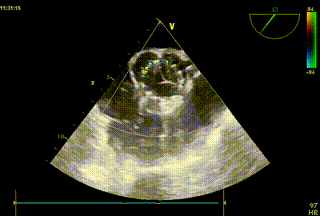

术后超声评估:

超声结合长轴短轴评估,无明显反流,瓣膜工作状态良好